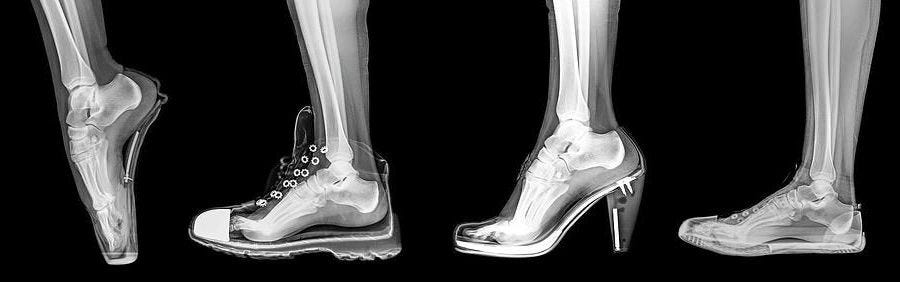

2. Qué hacen los zapatos

Las punteras aplastan los dedos.

Los tacones elevados alteran tu postura.

Las suelas evitan la retroalimentación del suelo.

El soporte del arco debilita los músculos.

Básicamente, te estás poniendo yesos en los pies todos los días.